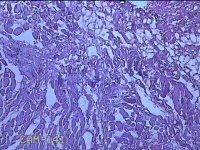

性别

男

年龄

26岁

临床诊断

皮脂腺囊肿

一般病史

发现前额部结节3年余。

标本名称

前额部结节

大体所见

灰白暗红色结节0.8x0.7x0.2cm一个,表面糜烂。

图2